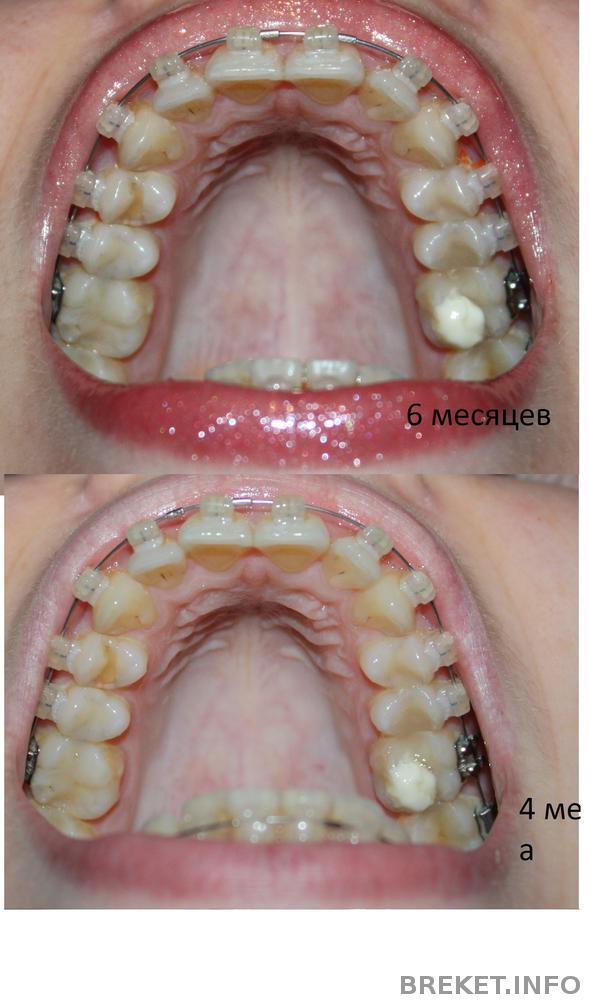

Всем привет! Пост будет коротким.... Неделя жуткая...((( От усталости, мне показалось, что моим зубкам 6 месяцев, сделала фотки, сравнила, немного расстроилась, что результат не такой хороший как мне хотелось бы....., Но все же он есть!!!, Из нового.., вчера мне поставили квадратную дугу на ВЧ и Пружину на НЧ , что бы делать место для одного зуба...., ЖУТКО БОЛИТ ВСЯ ЧЕЛЮСТЬ..., Никогда не болели так зубы с момента постановки БС..., но сейчас, это что то невыносимое, я не могу их смыкать..., а про покушать вообще молчу...((( голодаю одним словом...(( Прямоугольная дуга это жесть конечно...., но от нее жду хороших результатов!!!!

Прилагаю коллажи..., На которых как мне казалось, 6 месяцев, но посмотрев здесь, поняла что ошиблась на месяц...)) На фото нам 5 месяцев)))